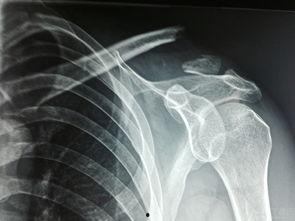

1. X光片上的“伤痕累累”:当你看到X光片上的锁骨,你会发现它就像被刀割过一样,断裂的地方清晰可见。

2. CT扫描下的“触目惊心”:CT扫描下的锁骨韧带断裂更加直观,断裂的韧带就像被拉扯过的橡皮筋,失去了原本的弹性。